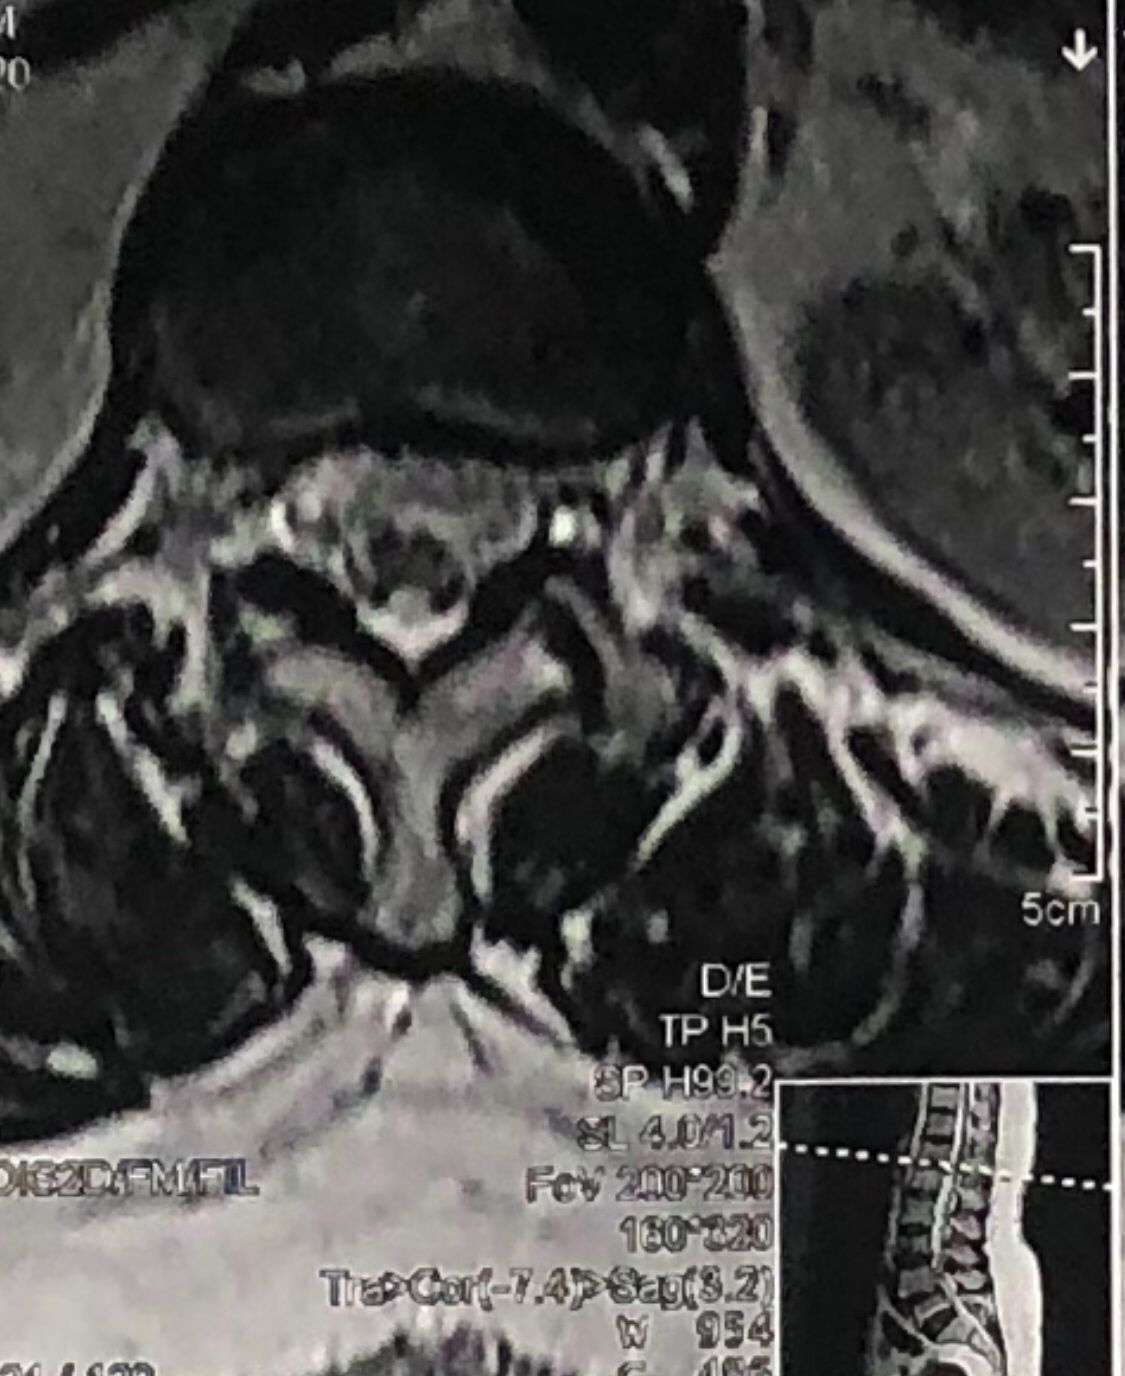

L4-L5 level:

sever L4-5 canal stenosis mainly due to FL hypertrophy?

CSF block. Mild L3 retrolisthesis, facets hypertrophy bilateraly causing L and R IVF stenosis, disc hyperbule